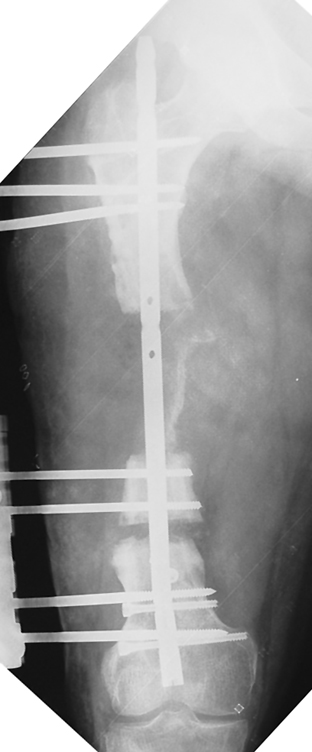

The duration of external fixation (external fixation index) depends on the amount of distraction required, and the extremity is prone to complications during this period. After the distraction phase is completed, the external fixator remains in place during the consolidation phase, which lasts twice as long as the distraction phase; but this period is hardly tolerated. If the external fixator is removed before sufficient consolidation is achieved, fractures, deformity and shortness will be the result. In our department, ‘lenghthening over nail’ method is used in order to decrease the external fixation index and increase patient comfort and activity level. In this method, the intramedullary nail is statically locked after the completion of the distraction phase, and external fixator is removed. The extremity is stabilized by the intramedullary nail during consolidation phase. In this way, complications due to long external fixation index or early removal of the external fixator are avoided.